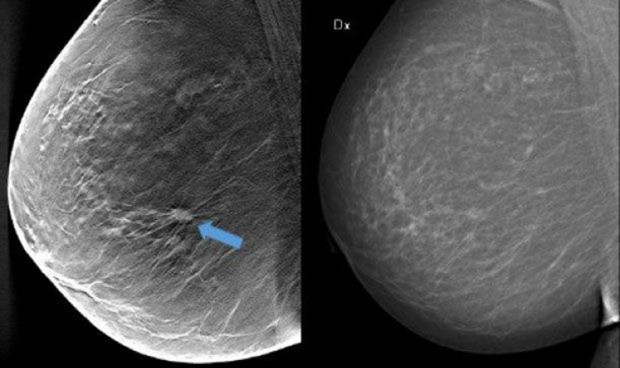

La calcificación arterial mamaria, la acumulación de calcio en la capa media de la pared arterial de la mama, está relacionada con el envejecimiento, la diabetes de tipo 2, la hipertensión y la inflamación, y es un marcador de la rigidez de las arterias. No es lo mismo que la calcificación de la capa interna de las arterias (la capa que está en contacto con la sangre), que suele darse en personas que fuman o con niveles altos de colesterol.

La calcificación de las arterias mamarias es un hallazgo común que aparece como áreas blancas en las arterias de la mama en una mamografía, sin embargo, no se cree que esté relacionado con el cáncer.